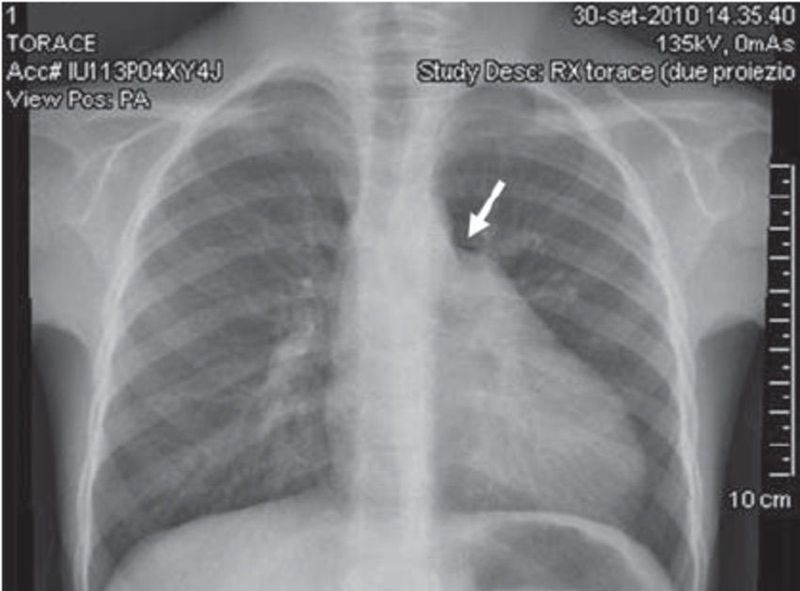

Chest X-ray showing the prominence of the left second cardiac arch, with an incision (arrow) between the first and second arch, due to the pericardial defect.